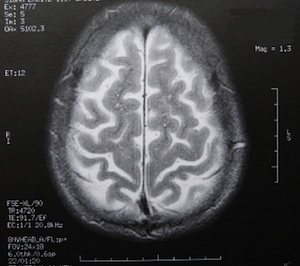

Mit dem Wohlstand wächst das Hirn

Bild: pixelio.de/Dieter Schütz